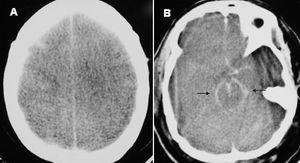

Mujer de 51 años que ingresa en el Servicio de Medicina Intensiva por una peritonitis difusa secundaria a una perforación instrumental del intestino delgado durante la reconstrucción laparoscópica de una colostomía. La paciente tuvo una sepsis grave con fracaso cardiovascular (hipotensión arterial de 95/50 mmHg con noradrenalina a 3 µ/kg/min), respiratorio (PaO2/FiO2 de 83), metabólico (pH 7,20 con exceso de bases -11), renal (oliguria < 0,5 ml/kg/h y creatinina de 2,7 mg/dl) y hematológico (trombocitopenia de 55.000/µl). El APACHE II fue de 28 puntos. En las primeras 24 horas de ingreso la paciente recibió 18 litros de cristaloides, coloides y derivados hemáticos. También se le administró dobutamina, midazolan, diprivan, imipenen, hidrocortisona y drotrecogina. Al tercer día de ingreso la paciente estaba en anasarca, con gran hinchazón facial y pupilas puntiformes. La presión arterial sistólica era de 115-120 mmHg, la presión venosa central de 24 mmHg, la saturación arterial de O2 del 84% (FiO2 de 1 y presión positiva al final de la espiración [PEEP] de 22 mmHg), la presión pico de la vía aérea de 45 mmHg (volumen corriente de 350 ml y 35 resp/min) y las presiones intraabdominales de 25 a 30 mmHg. Ante esta situación clínica, una laparotomía descompresiva realizada a pie de cama mostró ascitis, dilatación intestinal, congestión visceral y mínimo absceso subhepático. Tras drenar el absceso se dejó la laparotomía abierta y cubierta con una malla. En los hemocultivos del ingreso creció Escherichia coli. Aunque hubo una mejoría cardiorrespiratoria, al quinto día de ingreso apareció una midriasis arreactiva bilateral y, tras supresión de la sedación, se diagnosticó de muerte cerebral. Una TC craneal realizada sin contraste mostró un ECD y signos de HSA (fig. 1). La autopsia del cráneo puso de manifiesto un ECD y ausencia de hemorragias, abscesos o meningitis.

Figura 1. Una tomografía computarizada craneal realizada sin contraste que muestra edema cerebral difuso (A) y signos de hemorragia subaracnoidea dentro de las cisternas de la base (B).

La HSA produce en la TC craneal un aumento de la densidad radiológica del espacio subaracnoideo y de las cisternas de la base. Un patrón radiológico similar, pero en ausencia de una HSA verdadera (pseudo-HSA) puede observarse ocasionalmente en pacientes con ECD3. Cuando existe un ECD, como el que tuvo esta paciente, la TC craneal muestra una disminución global de la densidad cerebral que realza la nitidez de los grandes vasos sanguíneos intracraneales, lo que puede simular una HSA3. Puesto que el ECD contraindica la punción lumbar y la clínica tiene escaso valor en pacientes sedados y relajados, la distinción entre la pseudo-HSA y la HSA verdadera se basará en repetir la TC craneal con contraste, lo que aumentará la densidad de los vasos sanguíneos intracraneales en caso de pseudo-HSA3.